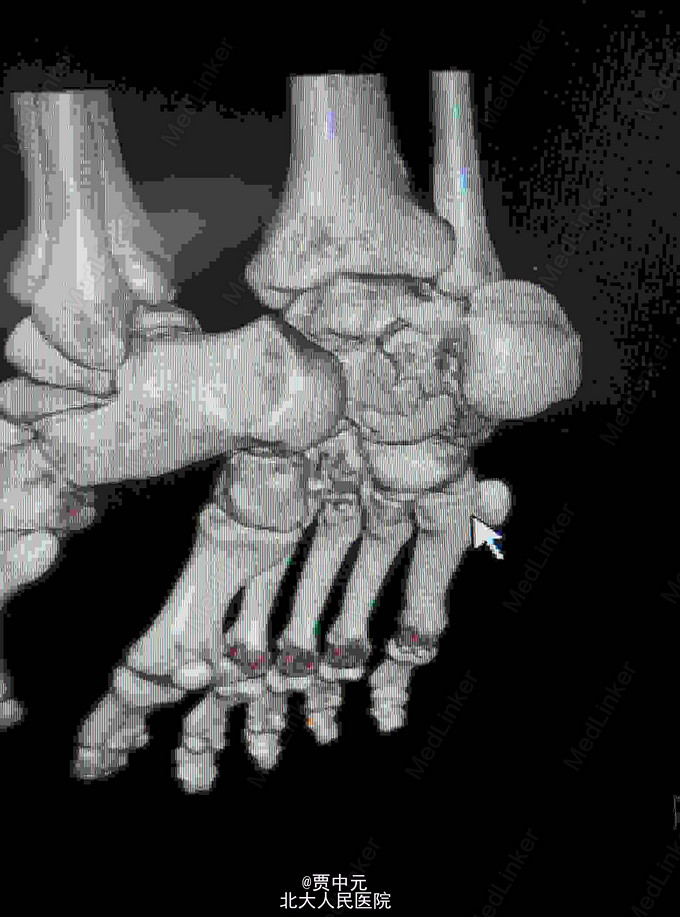

男性,31岁,主因“高处坠落伤致右足跟部疼痛,活动受限1天”于急诊以“右侧跟骨骨折”收入院。 一.病例特点 1.青年男性,高处坠落史。 2.患者约1天前自高处坠落右足着地,当时未昏迷,自觉右足肿痛,不敢活动,在当地医院拍片示:右侧跟骨骨折,为进一步手术治疗收住院。自入院来,患者无发热及胸闷憋气及腹痛症状

入院查体:右足跟部肿胀,局部皮下淤血,压痛,叩击痛,趾端血运可,足趾感觉及活动可,余肢体未见明显异常。 X线:右侧跟骨骨折(外院)

右侧跟骨骨折:高处坠落伤1天,查体:右足跟部肿胀,局部皮下淤血,压痛,叩击痛,趾端血运可,余肢体未见明显异常。 X线:右侧跟骨骨折(外院),根据外伤史,查体及X线检查,故此诊断明确

入院后考虑患者伤足局部软组织损伤重,皮肤条件欠佳,予以消肿,待皮纹征阳性后于今日在椎管内麻醉下行右跟骨骨折切开复位植骨内固定术。